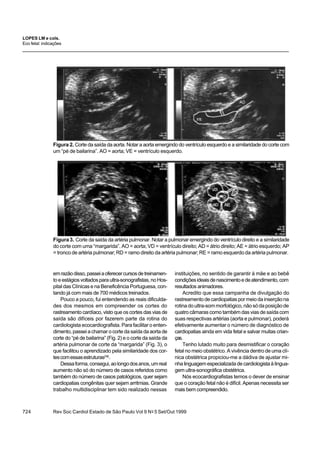

Figura 2. Corte da saída da aorta. Notar a aorta emergindo do ventrículo esquerdo e a similaridade do corte com

um “pé de bailarina”. AO = aorta; VE = ventrículo esquerdo.

Figura3. Corte da saída da artéria pulmonar. Notar a pulmonar emergindo do ventrículo direito e a similaridade

do corte com uma “margarida”. AO = aorta; VD = ventrículo direito; AD = átrio direito; AE = átrio esquerdo; AP

= tronco de artéria pulmonar; RD = ramo direito da artéria pulmonar; RE = ramo esquerdo da artéria pulmonar.

Pouco a pouco, fui entendendo as reais dificulda-

des dos mesmos em compreender os cortes do

rastreamento cardíaco, visto que os cortes das vias de

saída são difíceis por fazerem parte da rotina do

cardiologista ecocardiografista. Para facilitar o enten-

dimento, passei a chamar o corte da saída da aorta de

corte do “pé de bailarina” (Fig. 2) e o corte da saída da

artéria pulmonar de corte da “margarida” (Fig. 3), o

que facilitou o aprendizado pela similaridade dos cor-

tescomessasestruturas(14)

.